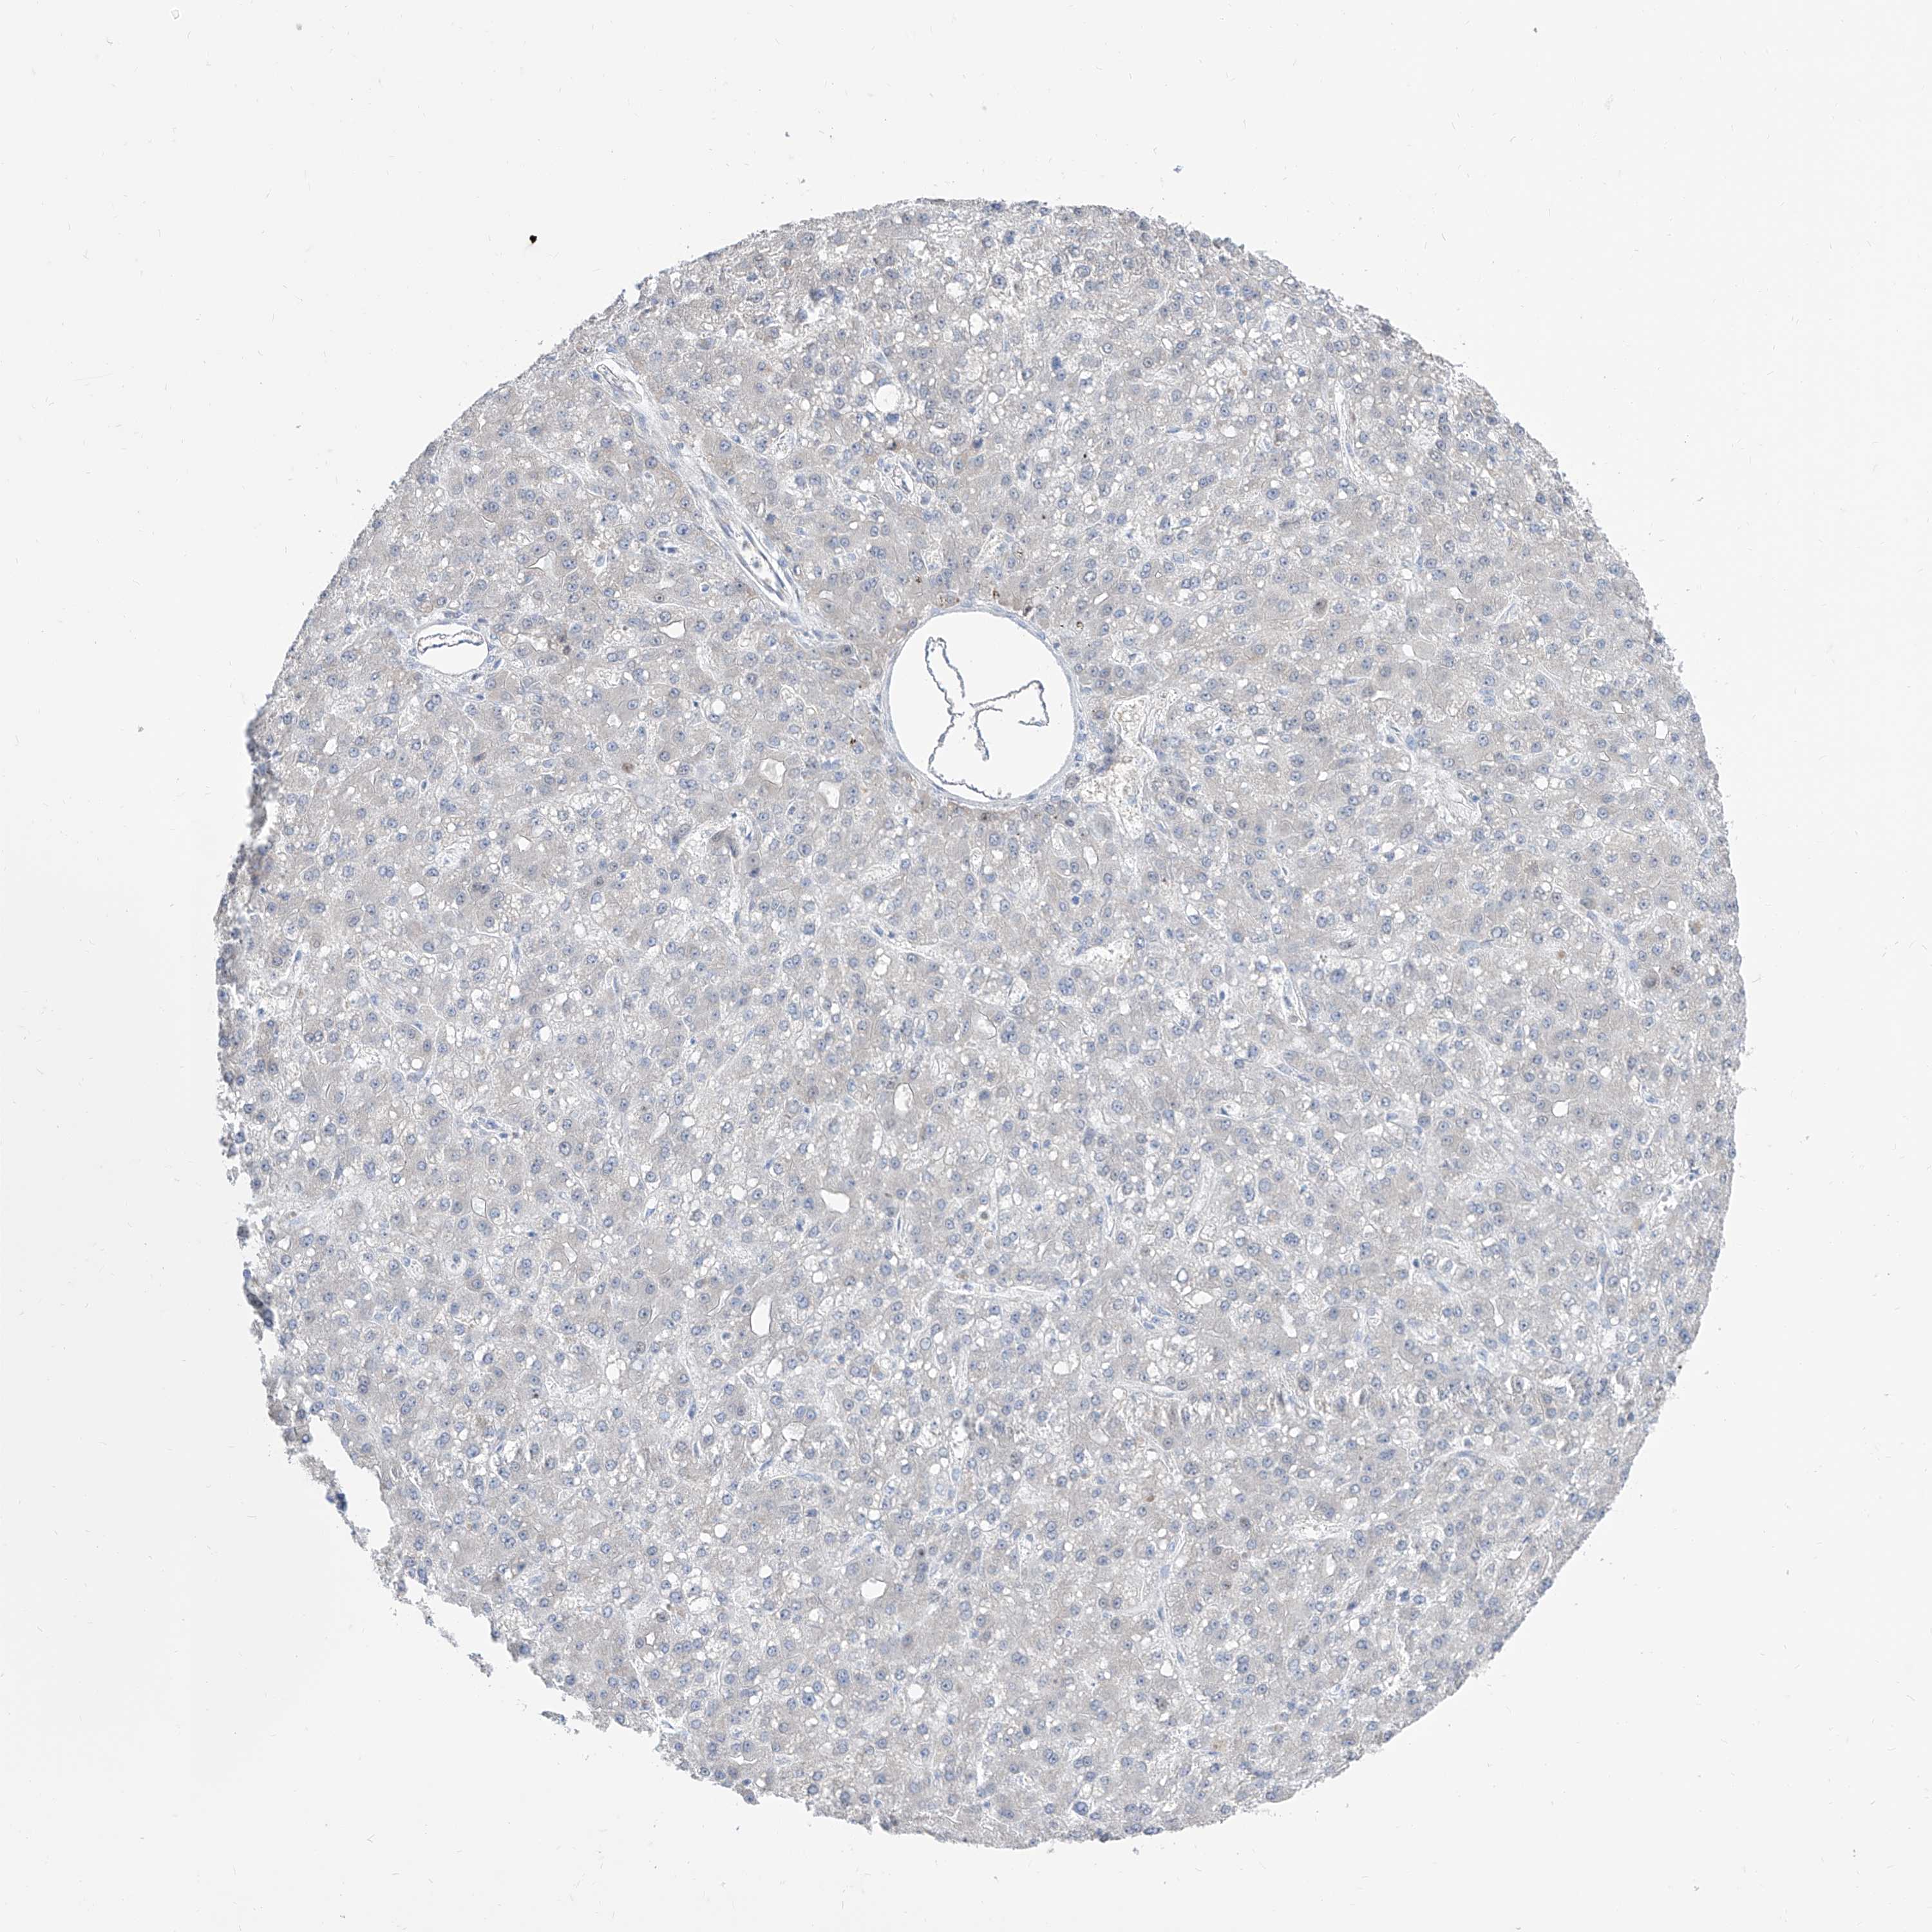

LIVER CANCER - Protein expressioni

A mouse-over function shows sample information and annotation data. Click on an image to view it in a full screen mode. Samples can be filtered based on level of antibody staining by selecting one or several of the following categories: high, medium, low and not detected. The assay and annotation is described here.

Antibody stainingi

Antibody staining in the annotated cell types in the current human tissue is reported as not detected, low, medium, or high, based on conventional immunohistochemistry profiling in selected tissues. This score is based on the combination of the staining intensity and fraction of stained cells.

Each image is clickable and will lead to virtual microscopy that enables deeper exploration of all samples and also displays staining intensity scores, fraction scores and subcellular localization as well as patient and tissue information for each sample.

Antibody HPA031445

Staining

High

Medium

Low

Not detected

Intensity

Strong

Moderate

Weak

Negative

Quantity

>75%

75%-25%

<25%

None

Location

Nuclear

Cytoplasmic/membranous

Cytoplasmic/membranous,nuclear

Cholangiocarcinoma

Carcinoma, Hepatocellular, NOS